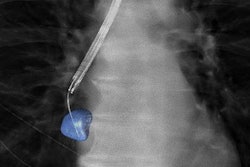

Bronchoscopy guided by conebeam CT and "augmented" fluoroscopy can be highly accurate in biopsying peripheral lung lesions. Also, a 3D CT reconstruction helped diagnose a rare tumor in a 17-year-old with jaw pain and swelling. Plus, a computer-aided navigation system was used by clinicians in Japan to successfully perform temporomandibular joint ankylosis surgery on a pediatric patient.